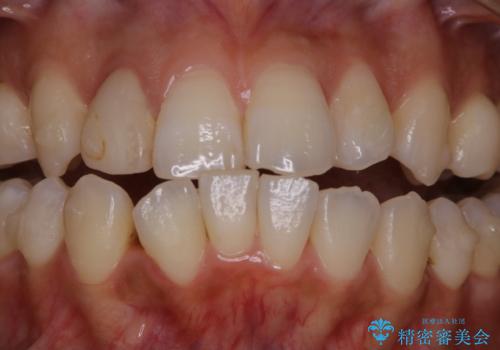

- インビザラインでのマウスピース矯正中の方です。歯についてしまったステインが気になり綺麗にしたいとのことでした。PMTC60分コースを行いました。

PMTC(保険外治療)は、毎日の歯磨きで落としきれない汚れや、コーヒ、紅茶・タバコのヤニなどの着色も除去します。目には見えない歯と歯の間・歯肉の境目・インビザライン中はアタッチメント周囲などに残っているプラーク(歯垢)もしっかり取り除きます。PMTCでは専門的な機械や材料を使用して、徹底的に汚れを除去するため、虫歯・歯周病・口臭予防などにつながります。

またPMTCを行うことで、ご自身本来の歯の色になり自然な明るさになります。